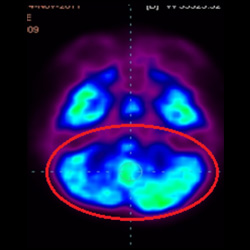

細(xì)胞治療前PET CT掃描顯示神經(jīng)組織中的藍(lán)/黑色區(qū)域,表明腦癱引起的大腦損傷。

腦癱細(xì)胞療法, 腦癱治療